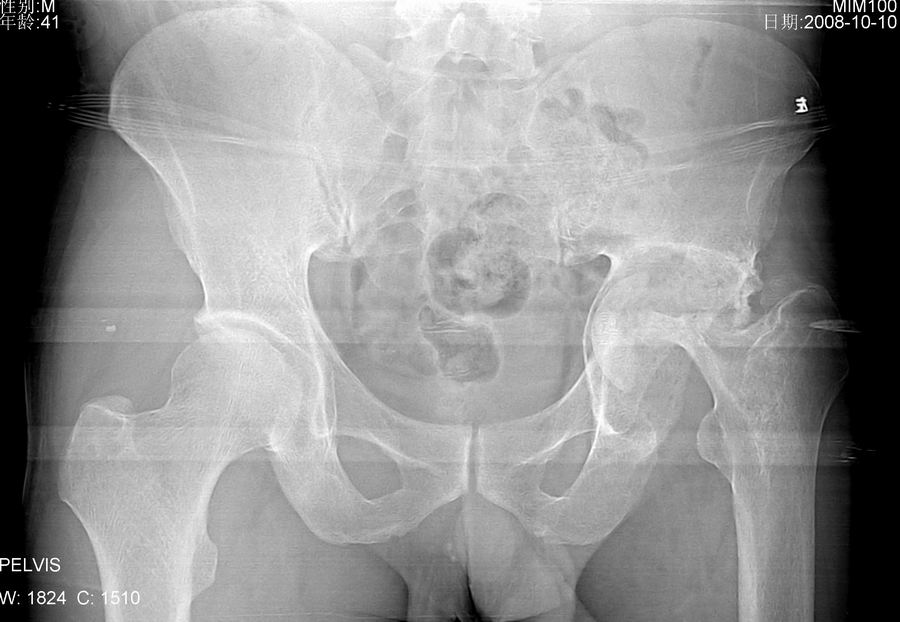

左髋关节疼痛,活动受限。

左髋臼增大,臼底变浅,股骨头及股骨颈骨质破坏并病理性骨折,臼上缘软组织内见机化样影,没见过这种改变,病史不祥,考虑左髋感染性病变可能,期待结果。

结果:髋关节结核

左髋臼增大,臼底变浅,股骨头及股骨颈骨质破坏并病理性骨折,臼上缘软组织内见机化样影,没见过这种改变,病史不祥,考虑左髋感染性病变可能[结核可能性大],期待结果。

左髋臼增大股骨头及股骨颈骨质破坏上缘软组织内见机化样影 , 髋关节结核